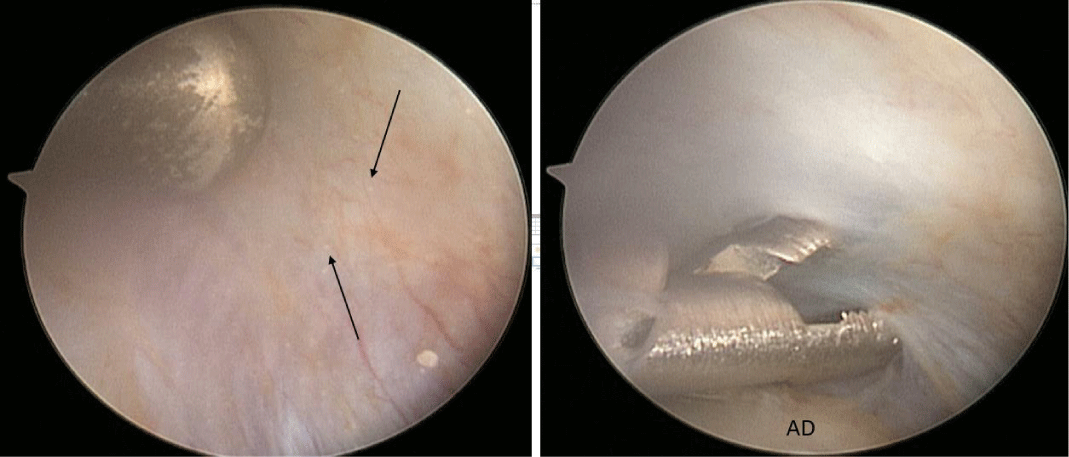

A 53-year-old male presented with a complicated musculoskeletal history consisting of head and neck dystonia and suprahyoid musculature spasms resulting in painful recurrent mandibular subluxation. Examination revealed a mouth-opening of 60 mm with ongoing subluxation due to muscle spasms. The CT scan of the left side suggested severe degenerative changes with multiple rounded erosive foci and a hazy periosteal reaction at the skull base (Figure 6). The T1 weighted MRI showed low signal intensity in the condylar bone marrow on the left. The disc was not visualized and there was no evidence of intra-articular mass (Figure 7). Diagnostic arthroscopy of the left showed a large central perforation of the disc with remarkable nodular synovitis. Synovial biopsy, synovectomy and debridement were performed (Figure 8). Histologic examination showed PVNS (Figure 9). Additional surgical treatment for the dislocation and the degenerative changes of the TMJ was deferred until further control of the muscular dystonia was achieved.

A 72-year-old female presented with left-sided jaw pain. Examination revealed tenderness over the left masseter, a mouth-opening of 35 mm and bilateral joint noises. Her left side had direct and indirect loading. The CT scan showed degenerative changes of the left condyle with a 2x2 mm subchondral cyst (Figure 10). The MRI revealed a degenerative left condyle with a deformed disc. The T2 weighted imaging showed a superior joint space effusion (Figure 11). Diagnostic arthroscopy showed retrodiscal synovitis, chondromalacia and a perforated disc. There were crystal-like structures within the synovium antero-medially. Synovial biopsy, debridement and partial synovectomy were performed (Figure 12). Histologic examination showed proliferative synovitis with calcium pyrophosphate deposition (Figure 13). The patient was referred for rheumatological management of CPPD but no treatment was initiated due to symptom resolution. On her 6-month follow-up her pain had resolved; she was maintaining a regular diet and her mouth-opening had become 45 mm with no joint loading.